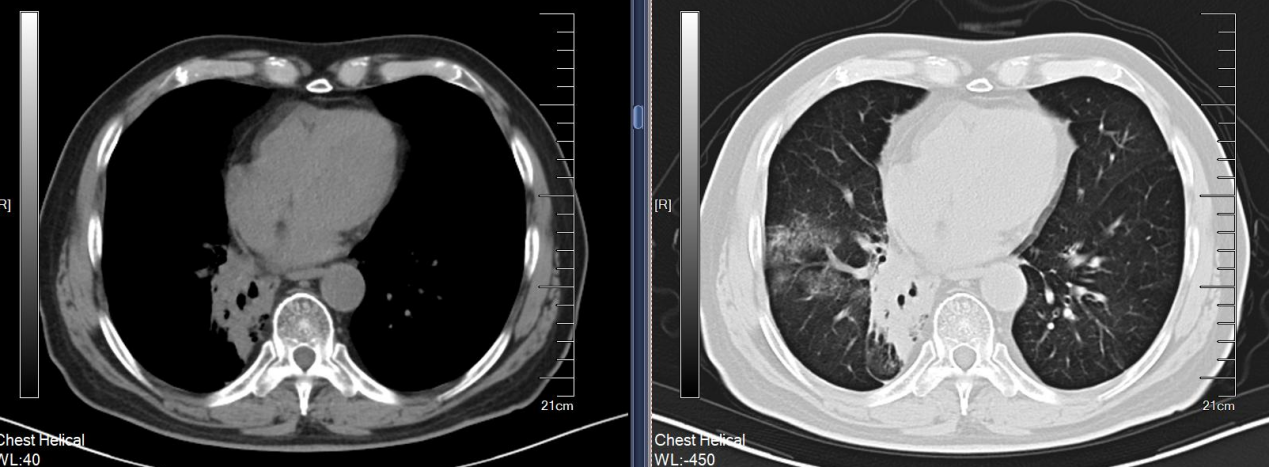

放疗:患者入院后完善相关检查检验,排除禁忌于2024年8月5日开始行放疗,靶区:右肺下叶病灶,剂量:50Gy/25Fx,于2024年9月6日完成放疗,放疗同期行白蛋白紫杉醇+卡铂治疗5周期,并予甘氨双唑钠增敏,期间出现化疗后骨髓抑制,经治疗后好转。治疗后患者咳嗽较前好转。

放疗前:2024年7月29日,PET-CT:右肺癌治疗后:1、右下肺门处软组织肿块,FDG摄取增高,结合病史,考虑肺癌伴伴肺不张伴远端阻塞性炎症,病灶仍具有肿瘤活性。 2、左肺上叶尖后段微小结节,FDG未见异常摄取,建议CT定期随访。 3、双肺肺气肿;双肺散在慢性炎症。 4、肝脏囊肿。 5、所示椎体退行性变。

图3. 放疗前影像

放疗后1月:2024年10月胸部CT:右肺下叶膨胀不全,右肺下叶肺门旁团块影,结合病史考虑肿瘤治疗后改变;2. 右肺上叶后段、左肺下叶背段慢性炎症伴局部支扩。

图4. 放疗后1月